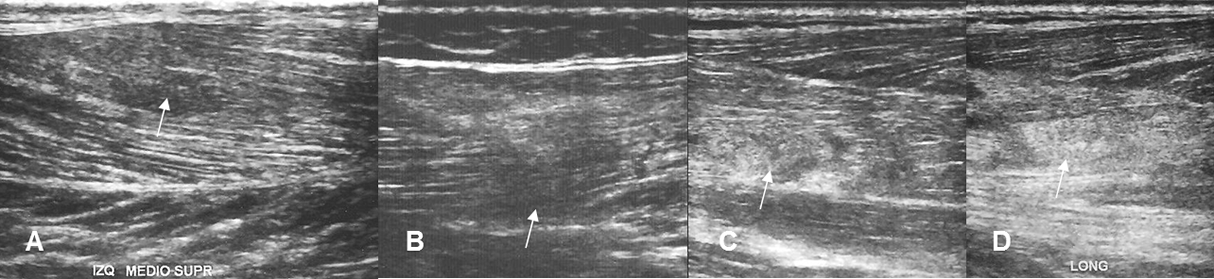

Fig 15 A. Distensión muscular grado 1.

A, B, C y D: Ecografías. Alteración del patrón fibrilar, por lesiones musculares G I. En A y B las fibras son hipoecoicas y en C y D, hiperecoicas.